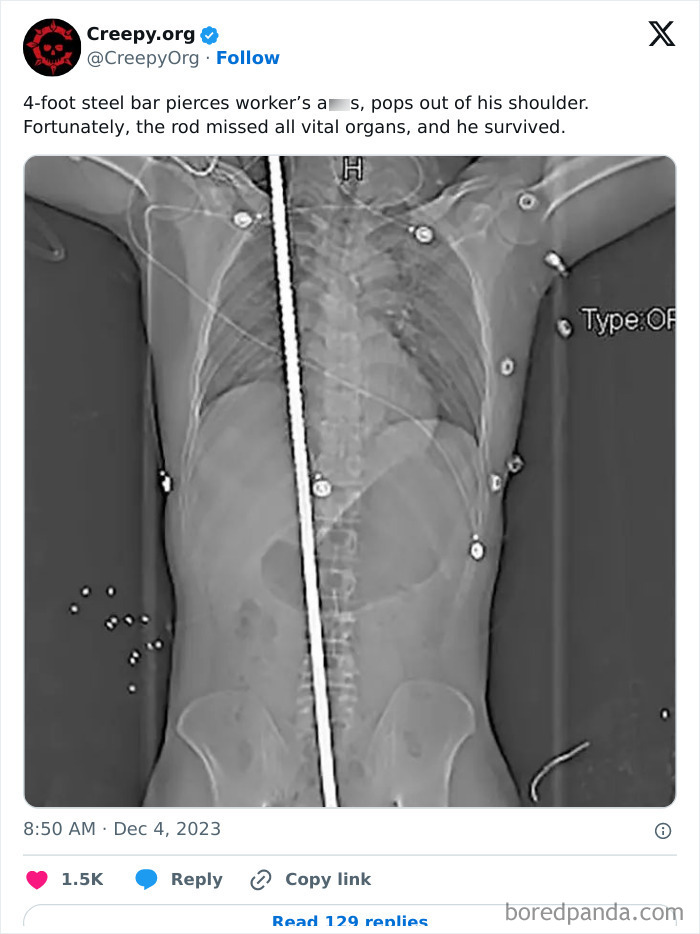

#2

Image credits: CreepyOrg